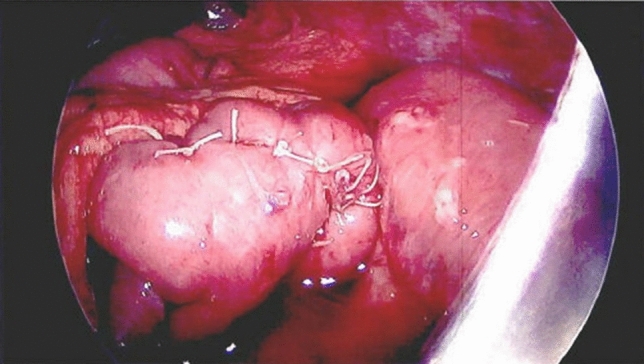

Methods and procedures: An 81-year-old Caucasian female was admitted to the emergency room with a complaint of 24-h epigastric pain, associated with nausea. She had history of a laparoscopic reduction of the foramen of Winslow internal hernia in our institution. CT scan of her abdomen showed a lesser sac internal hernia with an incarcerated colon and underwent a laparoscopic repair with a flap of falciform ligament and laparoscopic cecopexy. The surgery was successful.

Results: Foramen of Winslow hernias, a rare type of internal hernia. Internal hernias have an incidence rate of less than one percent, with Foramen of Winslow hernias accounting for only 8% of all internal hernias. The case at hand involves an 81-year-old Caucasian women who described a prior history of hypertension and a past laparoscopic reduction of the Foramen of Winslow internal hernia in the past. She had complaints of 24-h epigastric pain associated with nausea. She underwent a CT scan of her abdomen which revealed a lesser sac internal hernia with an incarcerated colon and was taken to the operating room where her Foramen of Winslow internal hernia was repaired laparoscopically using a flap of falciform ligament. The hernia contents included the ascending colon and ileum and were viable. A laparoscopic cecopexy and a flap of falciform ligament were done. The surgery was successful.

Conclusion: Foramen of Winslow internal hernias are exceedingly rare, as they account for approximately 8% of all internal hernias, which themselves have a precedence of less than 1%. Despite limited occurrence of Foramen of Winslow hernias, these hernias have mortality rates as high as 49%. Once diagnosed, several methods for repairing Foramen of Winslow hernias have been described. As surgical equipment and technology continue to improve, many surgeons have been switching from laparotomies to a laparoscopic approach. When the cecum shows signs of excessive movement, a cecopexy is often performed laparoscopically to limit such movement. In addition to cecopexy, a flap of falciform ligament was created in order to obliterate the space into the Foramen of Winslow. This novel approach has not been described in the literature. We strongly believe that it should be included as an option to treat these difficult hernias in the future.